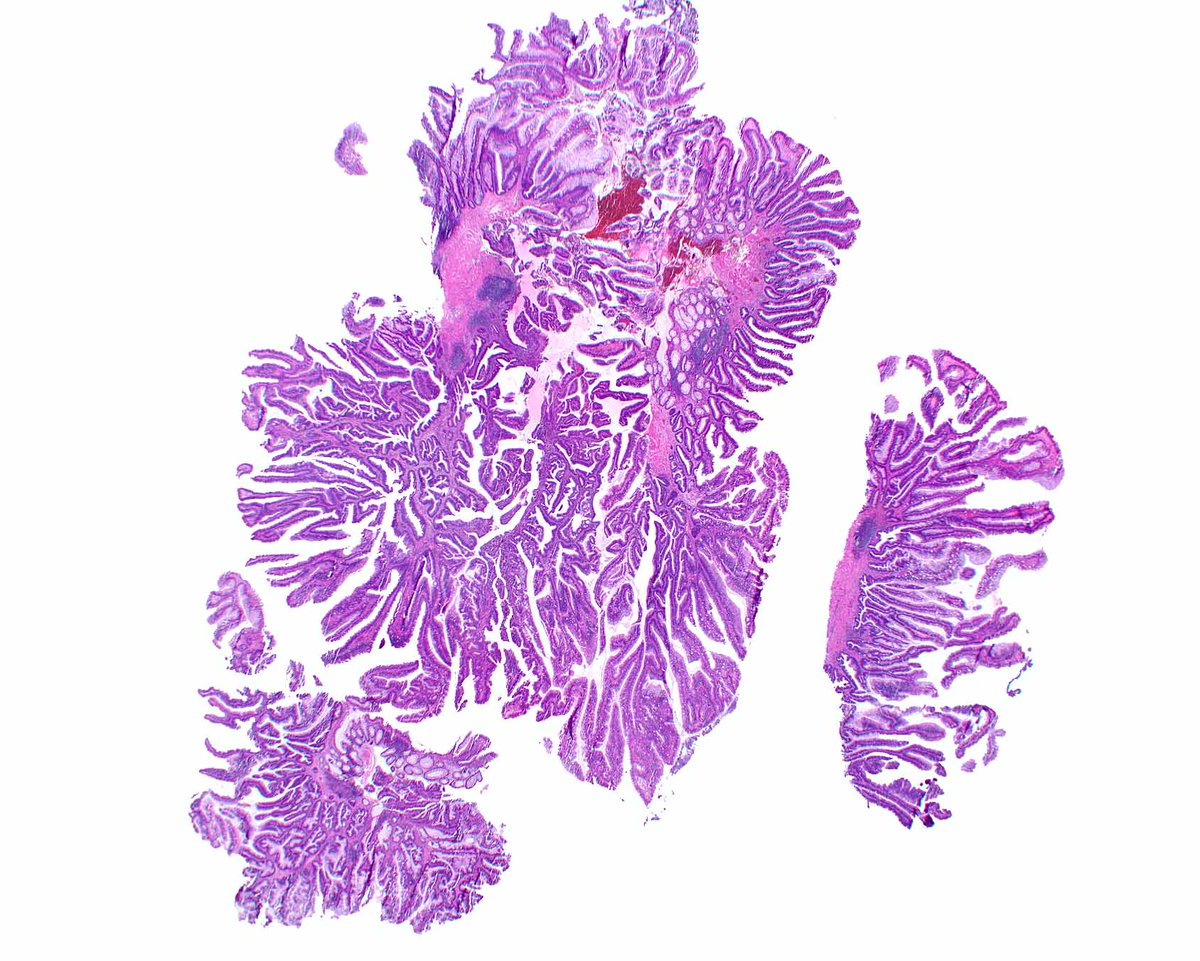

After a long Twitter hiatus because... life... I'm back to bring you this endometrial lesion in a 42 yo woman with abnormal uterine bleeding. Hysteroscopy showed an endometrial polyp in the lower uterine segment #GynePath #GynPath #PathTwitter

English